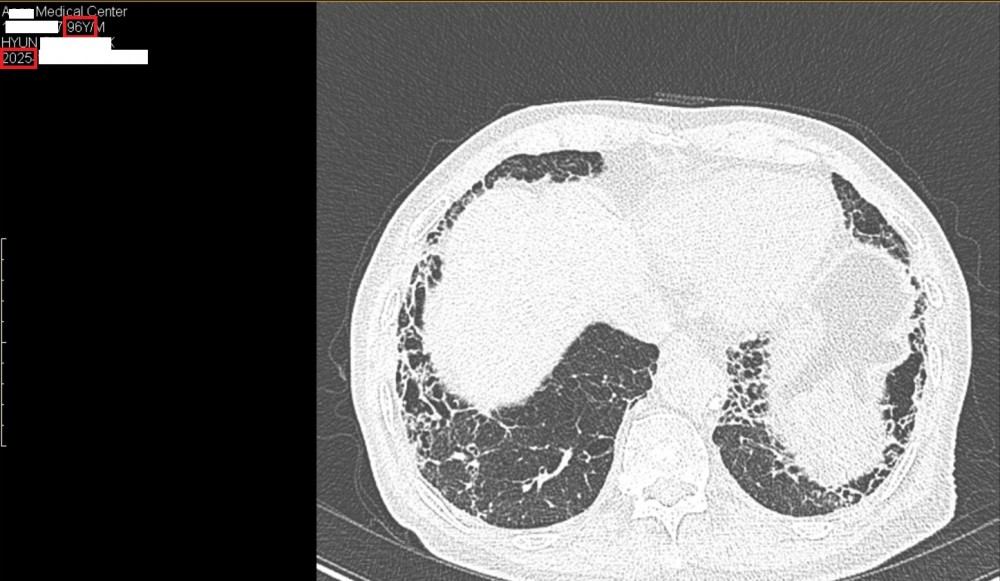

​폐섬유증 치료 받고 계시는 현00님의 따님께서 선물을 가지고 오셨습니다

2022년부터 숨케어한의원에서 관리 받고 계시는 분입니다

폐섬유증 관련해서는 피레스파 같은 양약을 복용하지 않고 한약만 복용하고 계시는데 잘 관리가 되고 있어서 다행으로 생각하고 있습니다

현재 숨케어한의원에서 폐섬유증 치료 받는 분 중에서 최고령(97세)입니다

2025년(96세) CT 사진